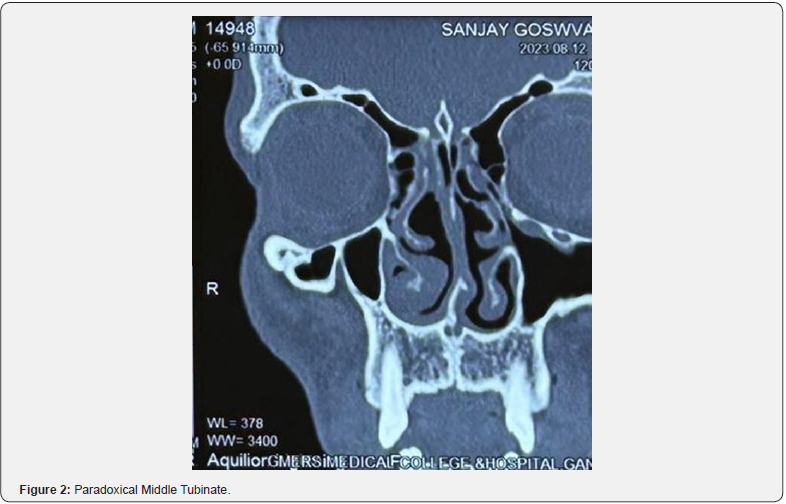

A retrospective study was conducted amongst 200 patients over a period of one year (2022-2023) at Sharda hospital Greater Noida . Patients with various symptoms of chronic rhinosinusitis were subjected to non-contrast enhanced Computed Tomography of nose and paranasal sinuses. Anatomic variations of the sinonasal cavities were assessed in the CT images, and prevalence of each was noted. The study included patients with age ≥ 18 having chronic rhinosinusitis and patient having chronic rhinosinusitis with or without polyposis who were advised NCCT nose and PNS after thorough examination. Patients having any previous nasal surgery or trauma, who did not consent for the study and patients less than 18 years were excluded from the study (Figure 2-4).

Middle turbinate

According to Mokhasanavisu et al. [14] concha bullosa was found in 64% and 52% of the populations of South and North India, respectively [14]. Azila A, et al. [8] in their recorded concha bullosa in 40.8% subjects having CRS and in 47.5% of control cases [8]. Amongst the Caucasians concha bullosa and paradoxical turbinate have been recorded as 12-31% and 10-22% respectively [15]. In our study, prevalence of concha bullosa was found 16.5%. However, paradoxical turbinate was present in 2.0% subjects. 90% of patients with concha bullosa had symptoms like headache, nasal obstruction, facial pain, which were relieved after surgical correction.